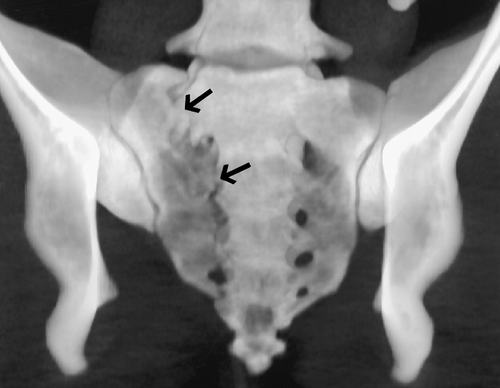

| Figures 12, 13. (12) Sacral fracture in a 34-year-old woman who was unable to walk or control her bladder after a high-speed motor vehicle accident. Anterior volume-rendered spiral CT image with the pubis and ischium removed by editing shows a fracture of the right hemisacrum that extends through the neural foramina of S1-S4 (arrows). The patient was ultimately able to walk but did not regain normal bladder control. (13) Anterior volume-rendered spiral CT image shows a sacral stress fracture. The fracture lines extend through both the left and right foramina of S1 and S2 (arrows). |